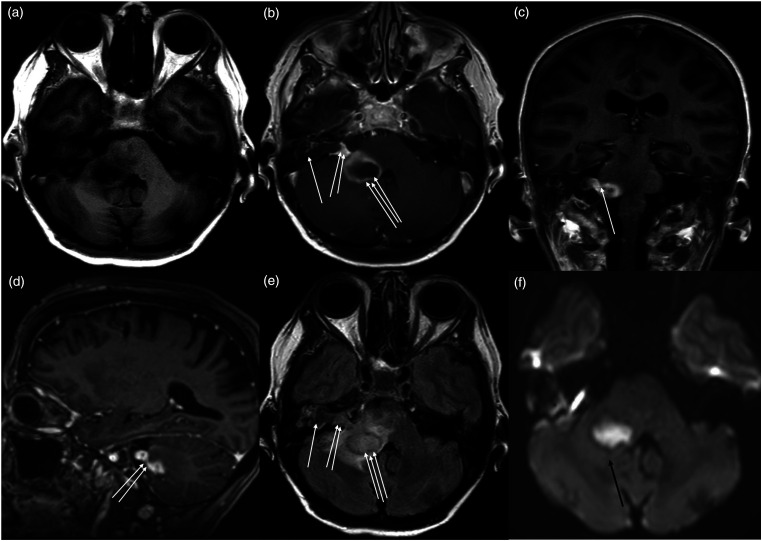

据报道,小脑脓肿是慢性化脓性中耳炎(CSOM)的一种并发症,有时会危及生命。小脑脓肿通常是由慢性化脓性中耳炎通过盆骨的骨质侵蚀或乙状窦的血栓性静脉炎直接传播引起的。然而,通过颅神经的解剖桥将感染从隐骨传播到小脑的另一种途径以前可能从未被描述过。一名患有 CSOM 和胆脂瘤的 63 岁女性患者出现共济失调和右侧面瘫。计算机断层扫描(CT)显示右侧耻骨骨质侵蚀,提示中耳感染。对比后磁共振成像显示,肿胀的第 7/8 神经复合物增强,提示神经炎,右侧岩骨有胆脂瘤。磁共振成像还显示同侧小脑脚有环形强化病变,提示脑脓肿。紧急进行了手术治疗,并抽出了脓液。随后,耳鼻喉科团队还为她进行了乳突切除术和胆脂瘤切除术,最终她的病情有所好转。本病例说明,CSOM 可通过颅神经的解剖桥传播感染而导致小脑脓肿,而不会直接从颞骨或鼻窦血栓性静脉炎侵入。

Cerebellar abscess is a reported complication of chronic suppurative otitis media (CSOM) and is life threatening at times. It usually develops by direct spread of CSOM through the bony erosion in the petrous bone or by thrombophlebitis of the sigmoid sinus. However, an alternative pathway of infection transmission from the petrous bone to the cerebellum through the anatomical bridge of the cranial nerves has possibly not been described before. A 63-year-old female patient with CSOM and cholesteatoma developed ataxia and right facial palsy. Computed tomography (CT) showed bone erosion of the right petrous bone suggesting middle ear infection. Post-contrast MRI revealed an enhancement of swollen 7th/8th nerve complex, suggesting neuritis, and cholesteatoma in the right petrous bone. It also showed ring enhancing lesion in the cerebellar peduncle of the same side suggesting brain abscess. Surgical intervention was performed emergently and pus aspirated. She also underwent mastoidectomy and removal of cholesteatoma later by the otolaryngology team and finally got better. This case illustrates that CSOM can cause cerebellar abscess by spreading infection via anatomical bridge of the cranial nerves without direct invasion from the temporal bone or thrombophlebitis of sinus.